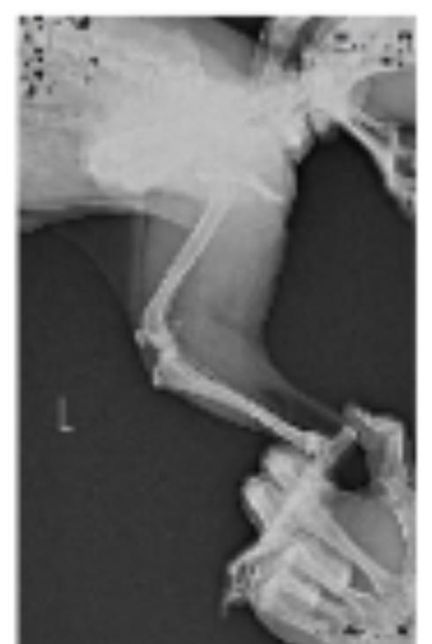

- 반려동물 건강반려동물순박한개개비238강아지 엑스레이 슬개골 탈구랑 십자인대 봐주세요ㅠㅠ저희집 강아지가 공놀이를 좋아하고 산책할때 좀 흥분해서 뛰는 편입니다ㅠㅠ 그래서 어릴때부터 슬개골이 좋지는 않고 1기에서 2기로 진행되고 있다는 얘기는 왕왕 들었는데 항상 꼬리를 들고 있는 앤데 꼬리도 내려가고 오른쪽 다리를 아파하는거 같고 산책나가서도 앉고 안걸을려고 해서 병원을 갔는데 슬개골 탈구랑 십자인대도 좀 안좋은거 같다고 영상기기 있는 곳애 가보라고 하셔서 가서 엑스레이를 찍어봤습니다..근데 그 병원에서는 슬개골이 안좋긴한데 삔거 같다고만 하셔서 약을 받아왔는데 그 뒤로 강아지가 꼬리를 드니깐 화들짝 놀라면서 싫어하는거 같더라구요...그래서 또 다른 병원을 갔느데 거기에는 또 영상기기가 없는데 슬개골탈구다 수술해야한다고만 얘기하셔서 혼란스럽네요ㅠㅠㅠ엑스레이 한번만 봐주실 수 있나요ㅠㅠ그리고 다리가 안좋을때 꼬리를 들면 다리가 더 아플 수 있나요?? 아니면 그냥 아파서 꼬리가 내려간걸까요...?? 후자면 다행인데 사람이 살살 들어봤을때 아파하는거 같아 허리 디스크에도 뮨제가 있는건 아닌지 걱정이 됩니다...ㅠㅠㅠㅠ1명의 전문가가 답변했어요